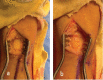

Figure 5

Anteromedial approach to the left distal tibia (a) and a window made in the distal tibia for AVN curettage (b–d).

Figure 6

Debridement and curettage of the distal tibia avascular necrosis.

Figure 7

Remplissage with bone graft (a) and reapplication of the cortical window (b).